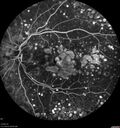

79 year old vision is in for a checkup with no visual complaints in the left eye. This is her better eye. VA 20/200 OD, 20/50 OS. 3 years ago she had a CRVO in the left eye. She is also diabetic for 20 years, has carotid insufficiency and anemia. Left eye shows CME. This was not treated and the vision improved to 20/40 over the next year although mild edema persisted.